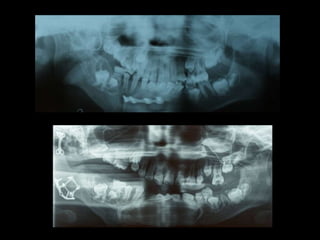

TC 3D

Hiperplasia condílea dcha

Anquilosis ATM dcha